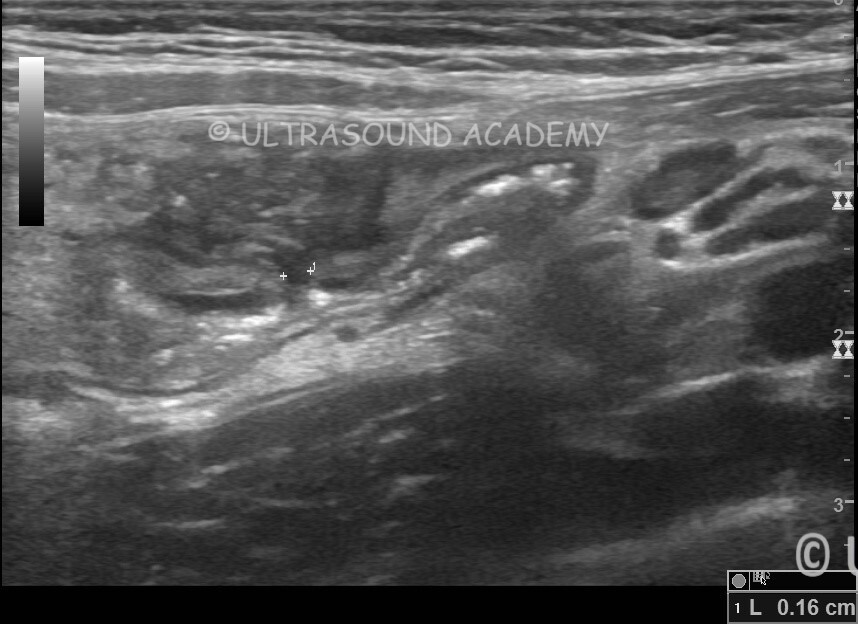

Meckel’s diverticulitis with Sealed off perforation

This is a 8 yr old child having complaints of right Iliac fossa pain.

This child was having similar complaint 1 month ago for which he underwent appendicectomy.

USG abdomen shows long tubular blind ending structure with gut wall signature at RIF. This structure was seen arising from terminal ileum confirming at as Meckel’s diverticulum.

Small discontinuity is seen within the wall of Meckel’s diverticulitis at its base S/O perforation. Small thick collection is seen adjacent to the perforation.

Meckel’s diverticulitis was confirmed on CT